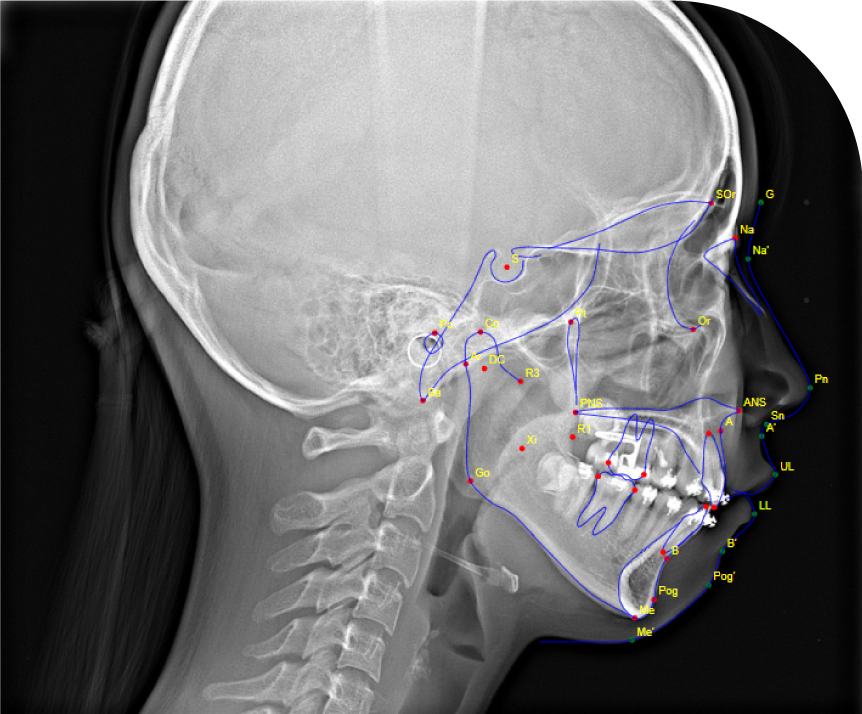

CEPH TRACING

Precise Cephalometric Analysis

Enhance your diagnostic capabilities with our Ceph Tracing service. We provide meticulous cephalometric imaging to support accurate orthodontic and orthognathic treatment planning. Our detailed tracings help identify skeletal and dental relationships, ensuring precise assessments for optimal treatment outcomes. Partner with us for reliable and comprehensive cephalometric imaging, improving patient care and treatment efficiency.